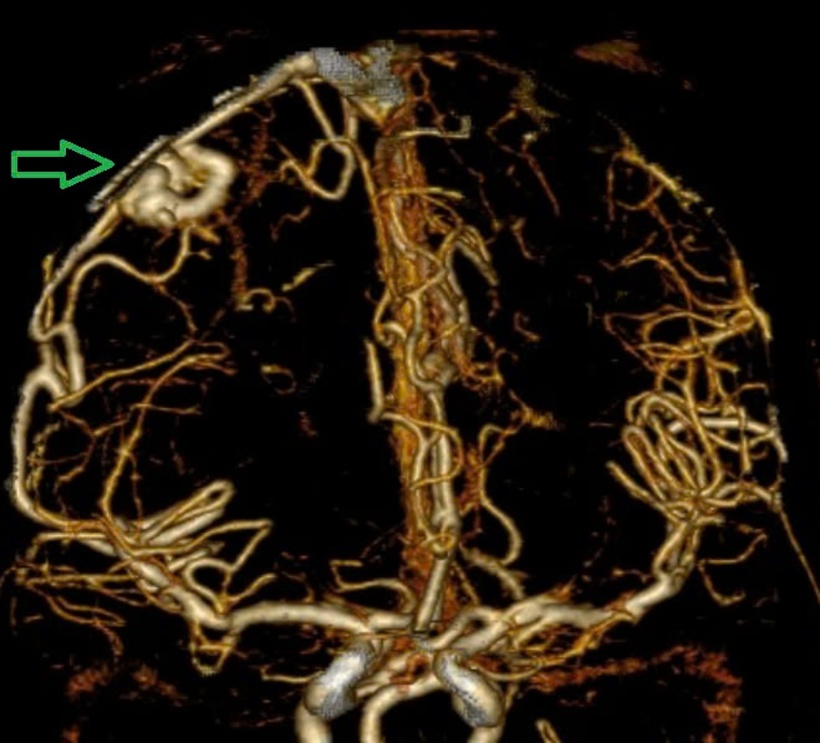

Một nữ bệnh nhân 29 tuổi, tiền sử khoẻ mạnh. Bệnh nhân đến viện vì đột ngột đau đầu, tê tay, nôn nhiều vật vã. Tại bệnh viện tỉnh, bệnh nhân được chẩn đoán chảy máu não, các bác sĩ đã đặt ống nội khí quản thở máy rồi chuyển tuyến lên Trung tâm Đột quỵ, Bệnh viện Bạch Mai trong tình trạng ý thức hôn mê, Glasgow 6 điểm, thở máy, đồng tử bên phải giãn 4mm, tụt huyết áp, duy trì vận mạch. Chụp MSCT mạch não: Chảy máu não thuỳ đỉnh phải, chảy máu não thất do vỡ AVM ( điểm Spetzler Martin 2 điểm). Bệnh nhân đã được phẫu thuật lấy máu tụ và khối dị dạng. Tuy được điều trị tích cực nhưng di chứng để lại vô cùng nặng nề. Sau một tháng điều trị, bệnh nhân chưa nhận thức được, liệt hoàn toàn nửa người trái…

Hình ảnh chụp MSCT mạch não: Chảy máu não thuỳ đỉnh phải, chảy máu não thất do vỡ AVM ( điểm Spetzler Martin 2 điểm) bệnh nhân nữ, 29 tuổi. Ảnh: BVCC